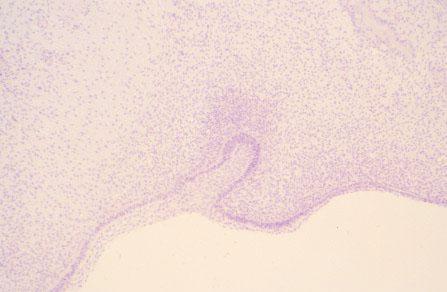

III-39 (4) Slide 45, Embryo, Developing Tooth. Medium power view. Stellate and spindle-shaped mesenchyme (undifferentiated connective tissue cells) are present in regions of soft tissue of the pulp chamber.